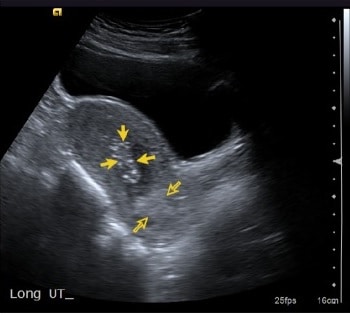

Fig 2 - Pelvic ultrasound scan. Retained products are demonstrated by the yellow arrows.

Pelvic ultrasound scan. Retained products are demonstrated by the yellow arrows.